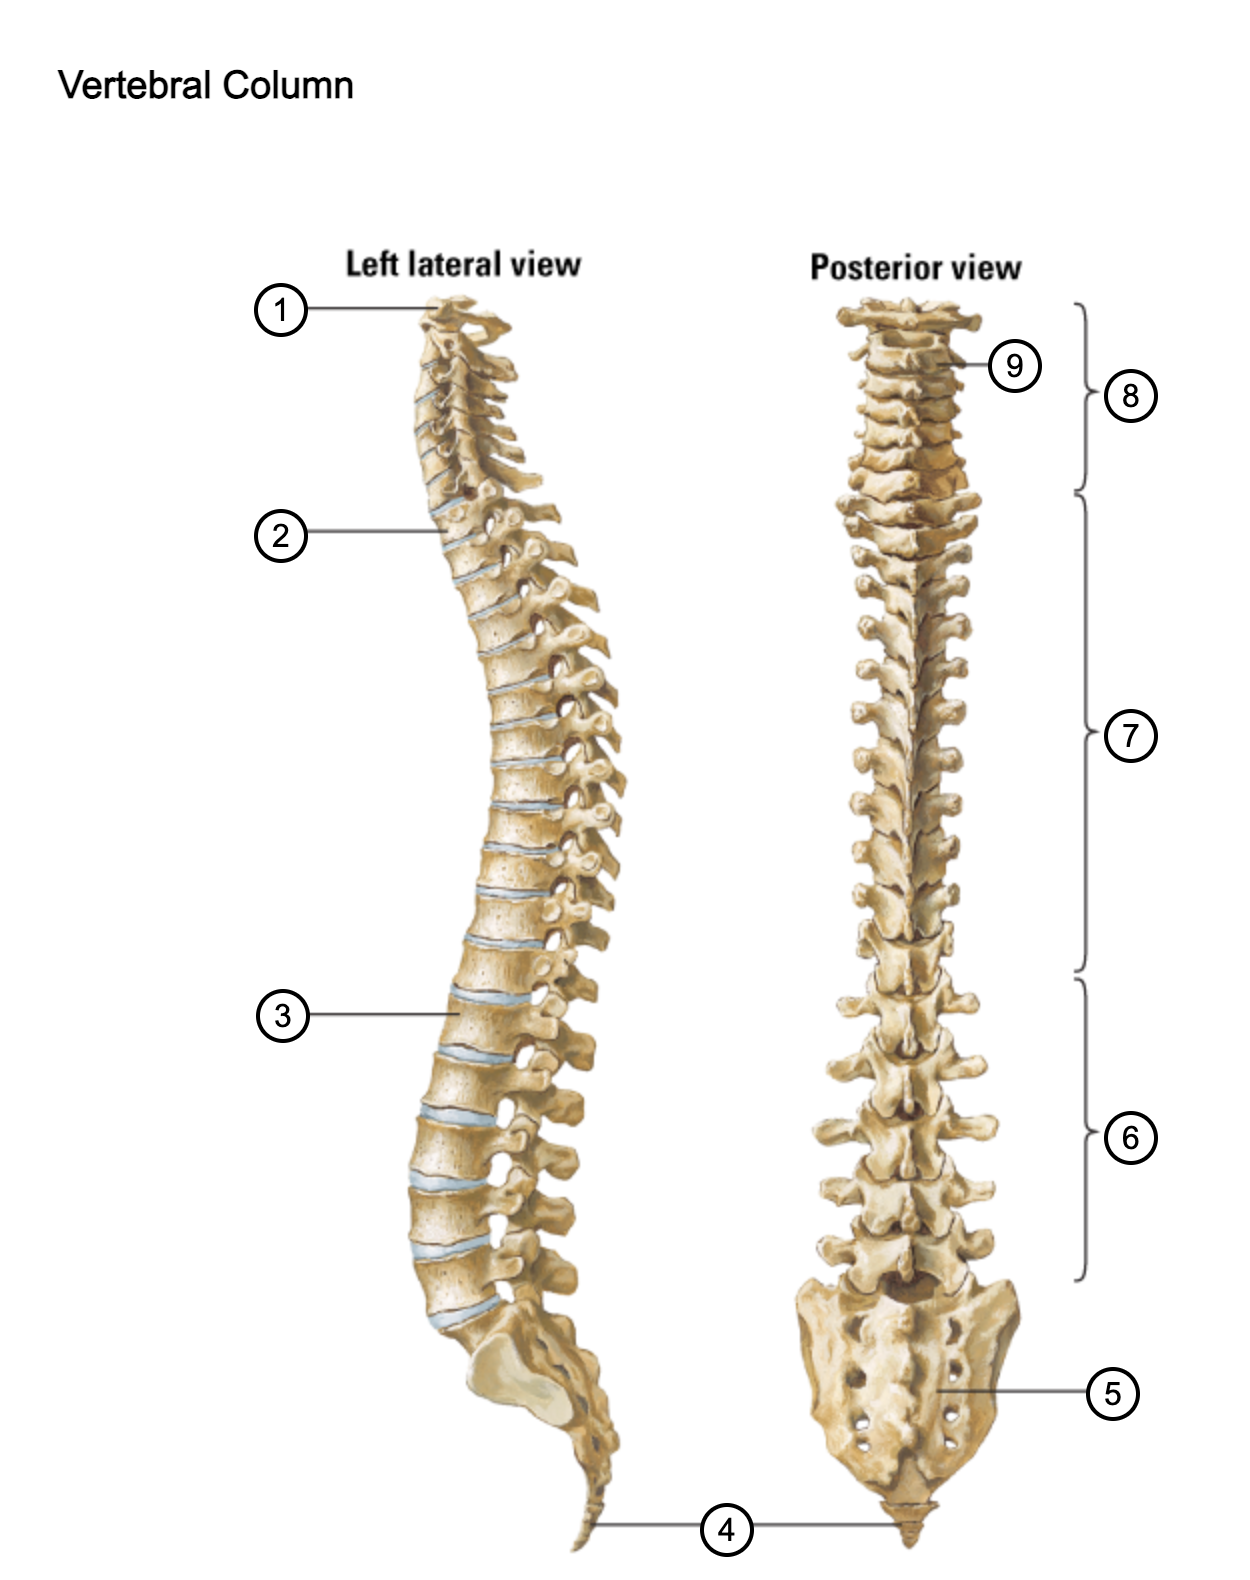

1

atlas (C1)

2

T1

3

L1

4

coccyx

5

sacrum (S1-5)

6

lumbar vertebrae

7

thoracic vertebrae

8

cervical vertebrae

9

axis (C2)